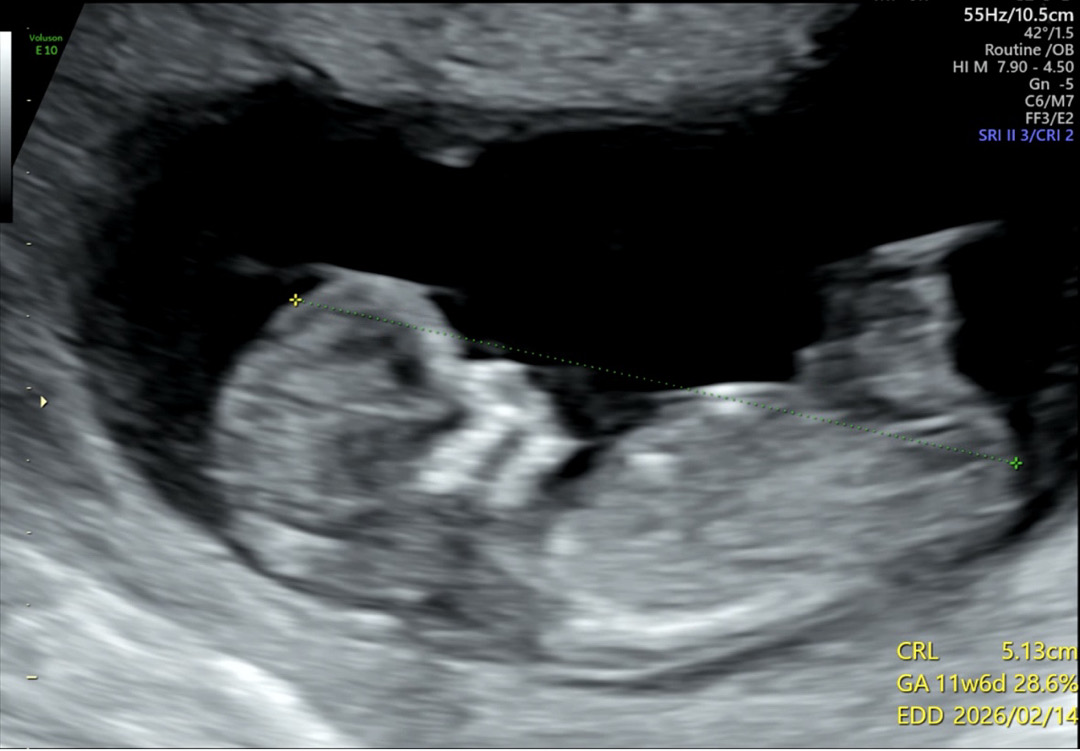

11주 6일인데 오늘 병원 다녀와서 촘파 봤어요 저는 각도법 하나도 모르겠던데 ㅠㅠ 봐주실 분 계시나욤